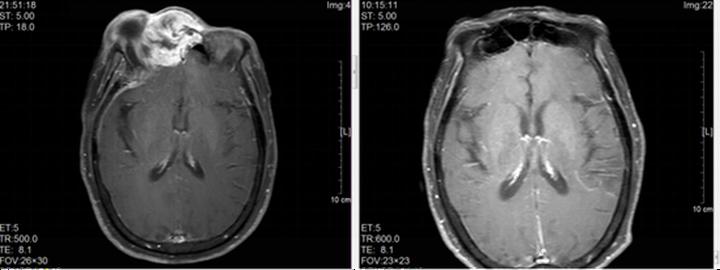

▲田阿姨接受治疗前、后的医学影像

治疗期间,田阿姨的症状逐渐缓解,3个月后复查,肿瘤已完全消退。如今五年过去,田阿姨不仅达到了临床治愈,还完好保住了双眼,日常生活和普通人一样,安享晚年。